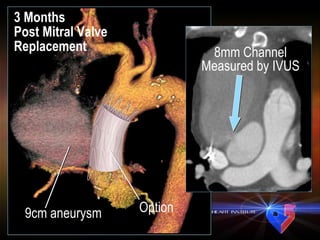

3 Months  Post Mitral Valve Replacement 9cm aneurysm 8mm Channel Measured by IVUS Option

Amplatz Occluder Retrograde femoral delivery Disc Diameter Ranges Small 12mm-30mm Large 14mm-32mm